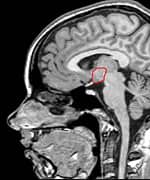

By sheer serendipity, many years ago Dr. Gordon provided care for a young man with a history of numerous sports-related head injuries, whose parents were themselves patients at the clinic. The young man's symptoms long outlasted the immediate effects of his acute injury and included loss of concentration, memory, mental energy, focus, and physical well-being, often accompanied by loss of lean muscle mass and an increase in body fat. The parents, familiar with the effects of hormonal imbalances, naturally assumed that their son's problems might reflect an endocrine problem of his own. And indeed, many of his symptoms resembled those of adult patients with so-called hypopituitarism, or loss of pituitary gland function. The pituitary gland is located at the base of the brain and is sometimes called the "master" gland of the endocrine system, because it controls the functions of the other hormone- secreting glands. Gordon, who is nothing if not intellectually curious, hit the books. What he found was startling and life-changing, for himself as a clinician, for his young patient, and now for scores of additional victims of traumatic brain injury. Symptoms of Traumatic Brain Injury Mimic Pituitary DysfunctionDr. Gordon found a wealth of published literature suggesting that traumatic brain injury causes pituitary dysfunction, confirming his initial hunch.1 Although the figures vary between studies, at least 50% (and up to 76%) of traumatic brain injury victims show some loss of pituitary hormone function immediately after the brain injury.2-4 In general, the more severe the original brain injury, the more profound the hormonal deficits, although hormone deficiency or insufficiency (levels in the low "normal" range) are seen even in patients with mild traumatic brain injury.5-9 And while about 58% of patients recover their normal pituitary function within one year of their head injury, a shocking 52% develop new pituitary hormone deficiencies after one year. 10,11 Those deficits include reductions in many different pituitary hormones, including those that regulate the thyroid gland, the adrenal glands (that produce cortisol, DHEA, and other vital hormones), the gonads (where estrogen and testosterone are produced), and growth hormone.3,4,12,13 The severity of the hormone deficiencies correlates strongly with the kinds of symptoms Dr. Gordon was seeing in his patient. For example, patients with growth hormone deficiency or insufficiency had significantly worse disability rating scores, greater rates of depression, worse quality of life, lower energy, greater fatigue, and poorer emotional well-being, compared to brain injury patients with normal hormonal levels.14,15 Dr. Gordon's hunch was borne out: patients with traumatic brain injury often have pituitary hormone deficiencies or insufficiencies, especially in growth hormone. And those defects are closely associated with the persistent neurological, psychological, and emotional deficits that are so tragically common in survivors of traumatic brain injury. And where are you most likely to find a high concentration of survivors of traumatic brain injury? The United States military.